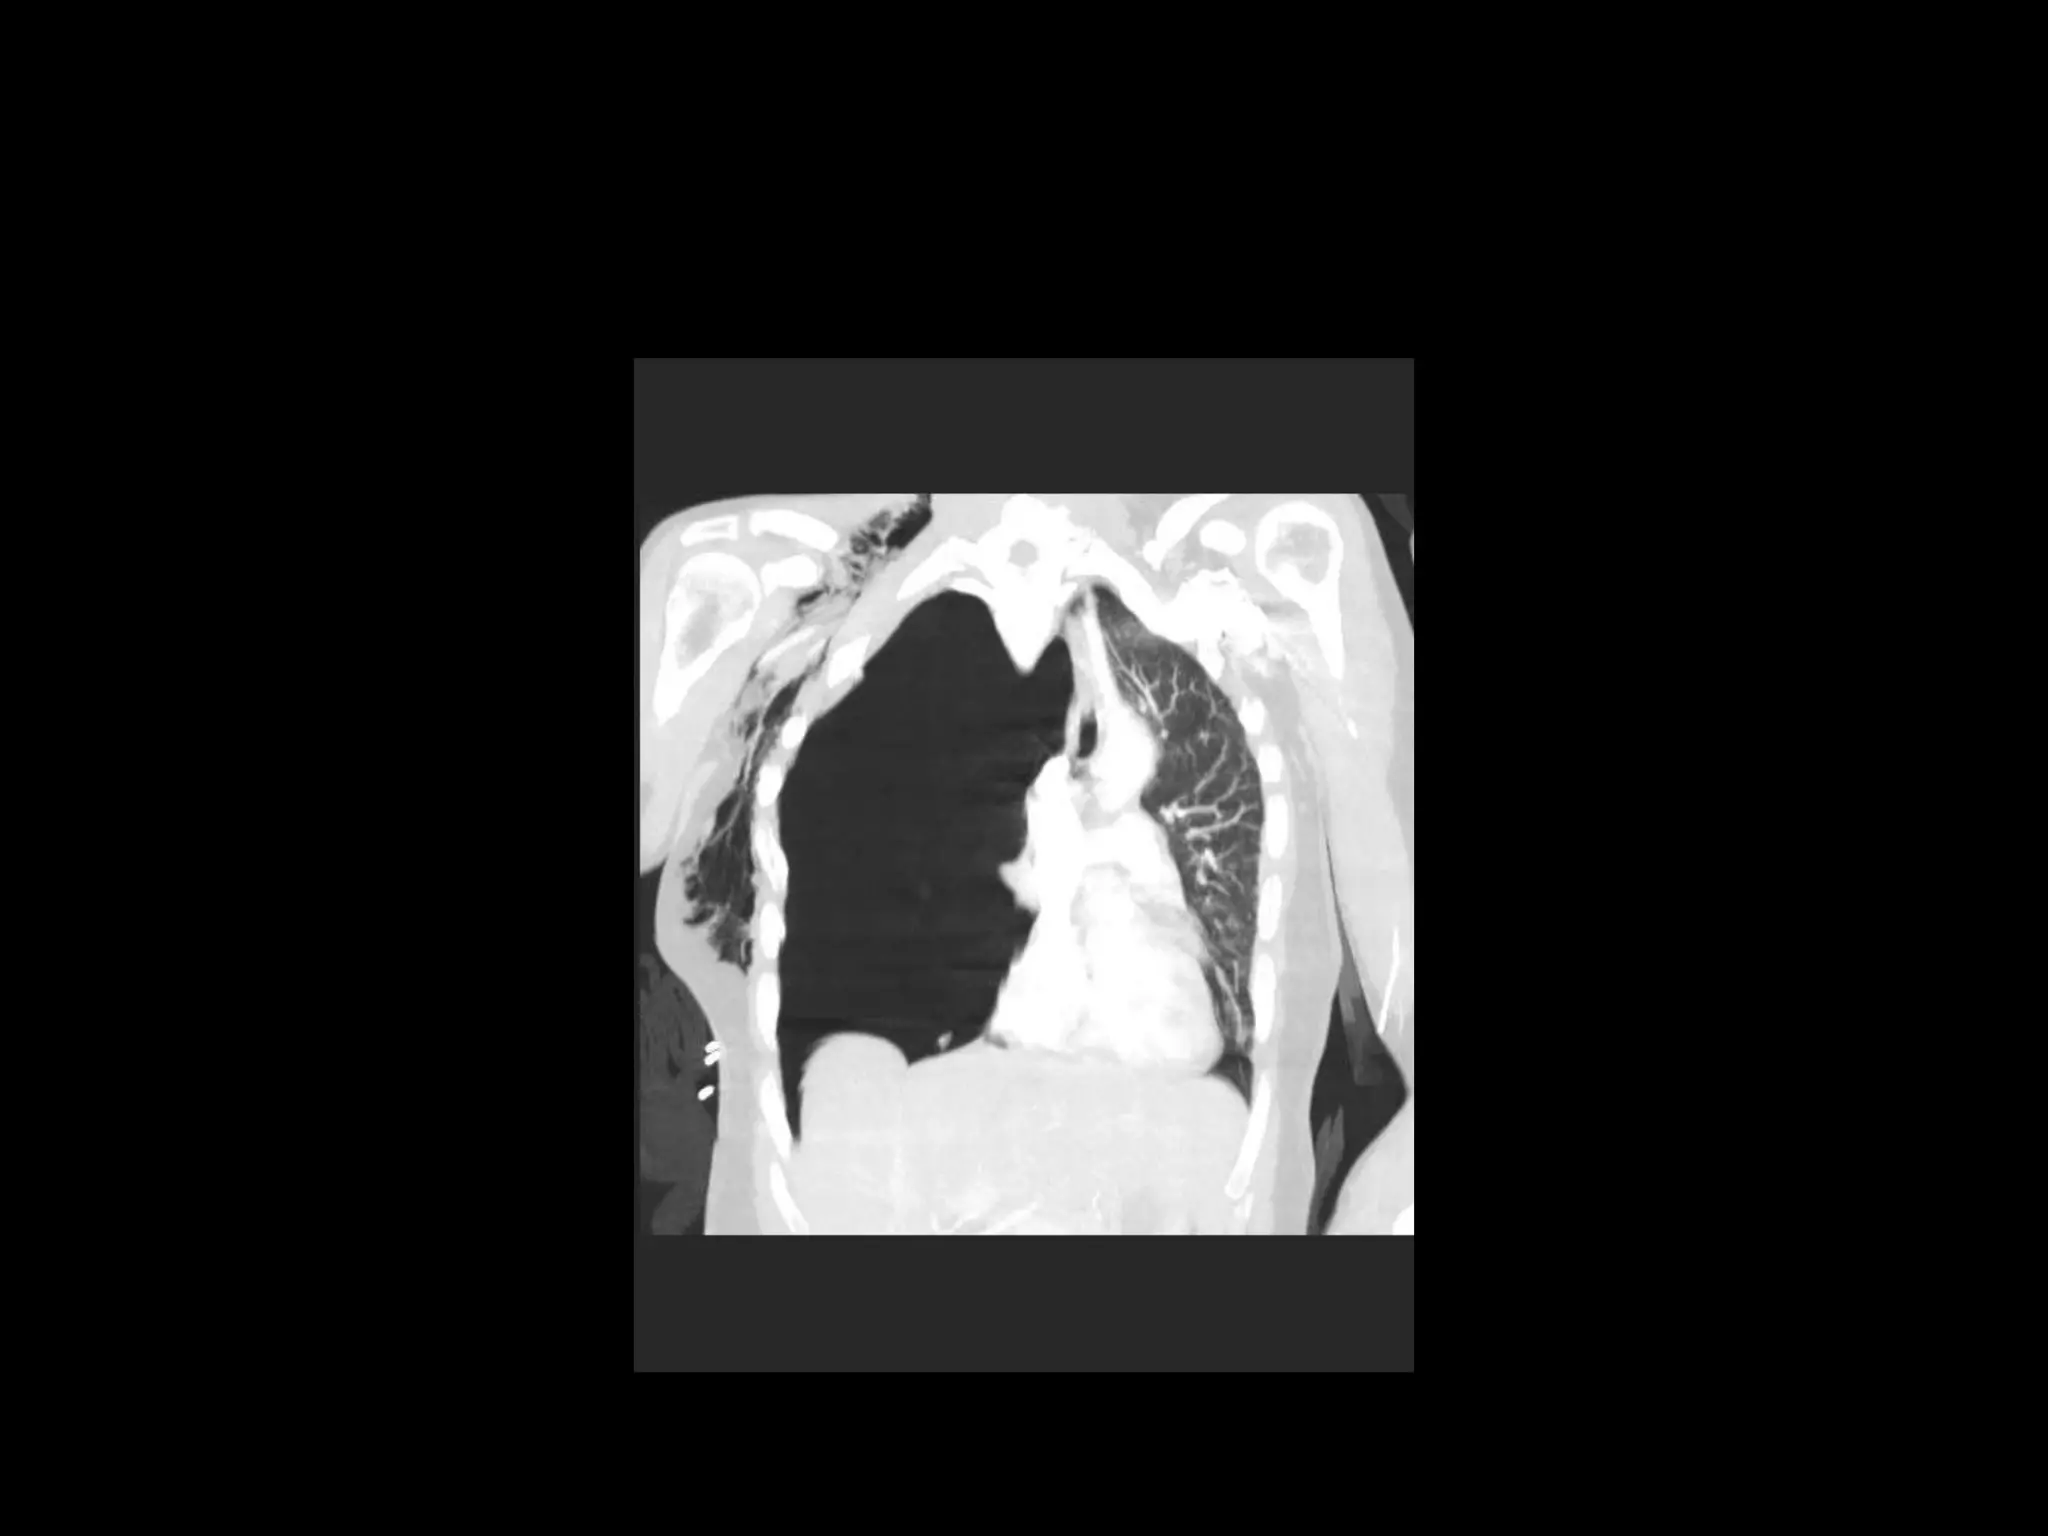

Chest X-ray

CT Scan - H1N1 Influenza

Pneumomediastinum

Ultrasound Findings

• Surgical emphysema

• Small pneumothorax

• Widespread patchy consolidation

• H1N1 pneumonitis